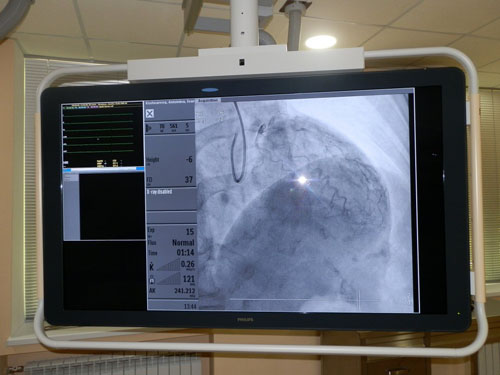

Как отметил заведующий отделениям Герман Веклов, подобных ангиографов экспертного класса в Украине - считанные единицы. Мощная техника позволяет на высоком уровне диагностировать сердечно-сосудистые заболевания, которые, как известно, являются одними из наиболее опасных.

"Аппарат предназначен для исследования сосудов. Принцип простой: вводится через катетер в проблемный сосуд рентген-контрастное вещество, и по мере заполнения этим веществом, виден дефект. Диагностируются бляшки, в том числе тромбозы", - сообщил Герман Веклов, врач-переселенец из Донецка, который до этого на протяжении года работал в Институте сердца в Киеве.

По его словам, с помощью ангиографа можно проводить и диагностическую, и лечебную процедуры.

"В случае острого инфаркта миокарда, после выявления тромба, проводится ургентное стентирование. То есть, в этот суженный участок вставляется пружинка, так называемый стент, который открывает артерию, и это спасает человеку жизни, храня жизнеспособный миокард. То же и при плановом обследовании – если мы смотрим, что там достаточно проблемное сужение, то мы выполняем это стентирование в кратчайшие сроки", - объяснил он.